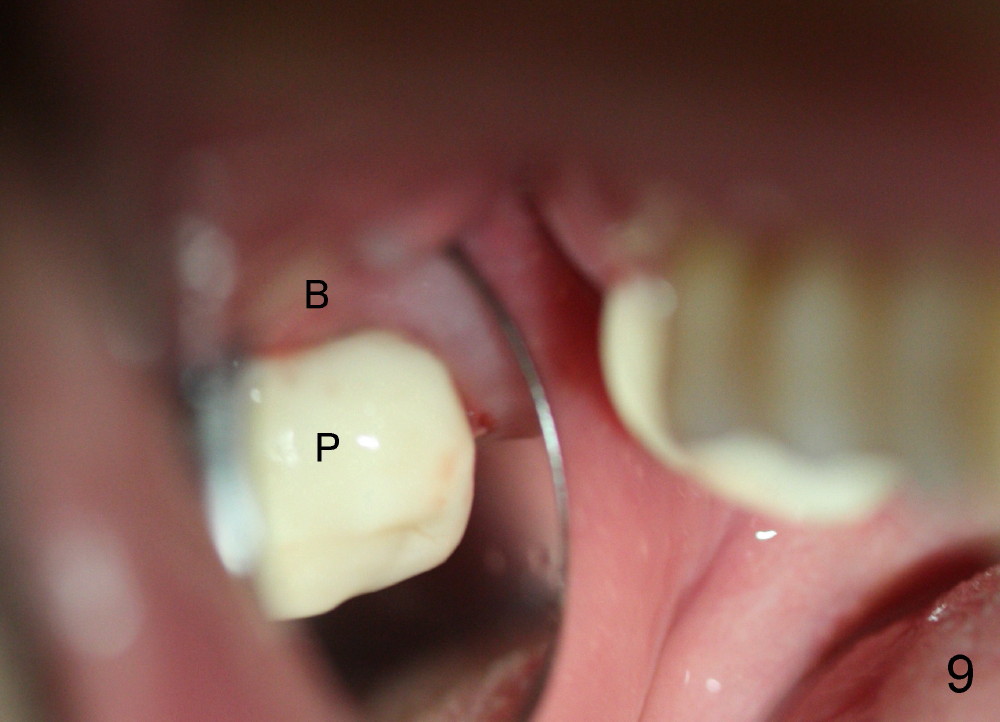

By contrast the palatal socket is deep and relatively small (Fig.4 P), easy to insert taps without drills. When a 7x11 mm tap is placed (Fig.5 T), the coronal end is more or less near the lingual cusps (functional cusps). Although the 7x14 mm tap (Fig.6 T) and a 7x11 mm implant (Fig.7 I) look poking into the maxillary sinus, they are in fact within the palatal socket (Fig.10c). Allograft and Osteogen are placed in the buccal socket (Fig.7 *), followed by collagen dressing (Fig.8 *). A 5x5 mm abutment is placed (Fig.8 A). An immediate provisional (Fig.9 P) is cemented to keep the graft and collagen dressing in place.